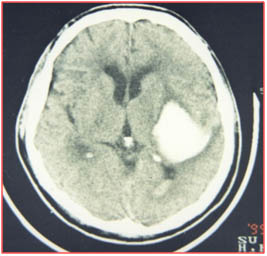

高血壓腦出血的外科治療 外科治療適應(yīng)項(xiàng)目: 1.清除血腫,解除對周圍腦組織的壓迫; 2.降低顱內(nèi)壓(ICP),改善腦血流; 3.解除急性梗阻性腦水腫; 4.解除和防止腦疝。 手術(shù)早期清除血腫能降低血液和血漿產(chǎn)物的毒性作...

高血壓腦出血的外科治療 外科治療 適應(yīng)項(xiàng)目: 1.清除血腫,解除對周圍腦組織的壓迫; 2.降低顱內(nèi)壓(ICP),改善腦血流; 3.解除急性梗阻性腦水腫; 4.解除和防止腦疝。 手術(shù)早期清除血腫能降低血液和血漿產(chǎn)物的毒性作...